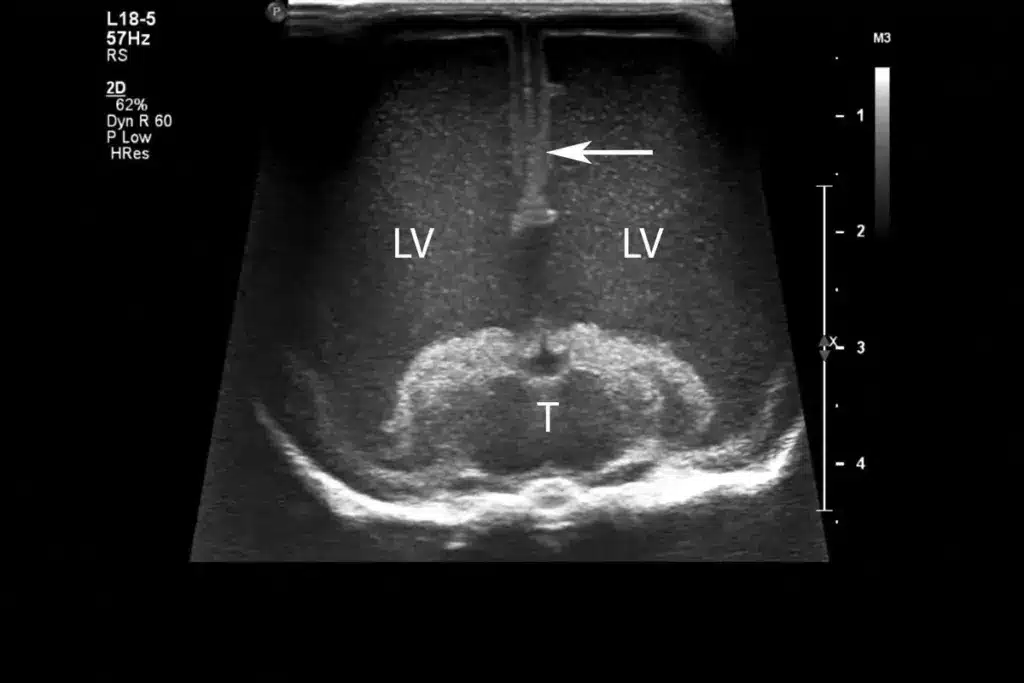

Hydrocephalus is a condition where too much cerebrospinal fluid (CSF) builds up in the brain. CSF is a clear fluid that protects the brain and spinal cord. In hydrocephalus, the CSF doesn’t flow right, causing it to build up. This can make the brain’s ventricles get bigger.

Cerebrospinal fluid (CSF) is essential for brain health. It protects the brain, controls pressure, and removes waste. In hydrocephalus, CSF issues can harm brain function.

CSF balance is vital for brain health. Disruptions can cause hydrocephalus, where CSF buildup presses on the brain, affecting thinking.